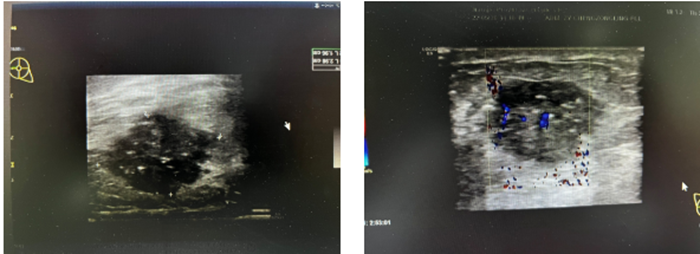

形态不规则,边界部分成角,条状血流信号,BI-RADS  5类